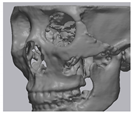

2.2. Computer-Aided Virtual Surgery, Design, and Fabrication of Patient-Specific Devices

2.3. Surgical Procedure

2.5. Cone Beam CT and 3D Comparison